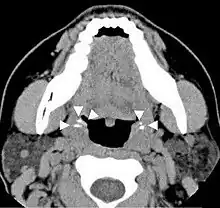

Imaging diagnostic techniques can identify a radiopaque mass that may be mistaken for foreign bodies, displaced teeth or calcified blood vessels. CT scan may reveal nonspecific calcified images in the tonsillar zone. The differential diagnosis must be established with acute and chronic tonsillitis, tonsillar hypertrophy, peritonsillar abscesses, foreign bodies, phlebolites, ectopic bone or cartilage, lymph nodes, granulomatous lesions or calcification of the stylohyoid ligament in the context of Eagle syndrome (elongated styloid process).[18]

Differential diagnosis of tonsilloliths includes foreign body, calcified granuloma, malignancy, an enlarged temporal styloid process or rarely, isolated bone which is usually derived from embryonic rests originating from the branchial arches.[19]